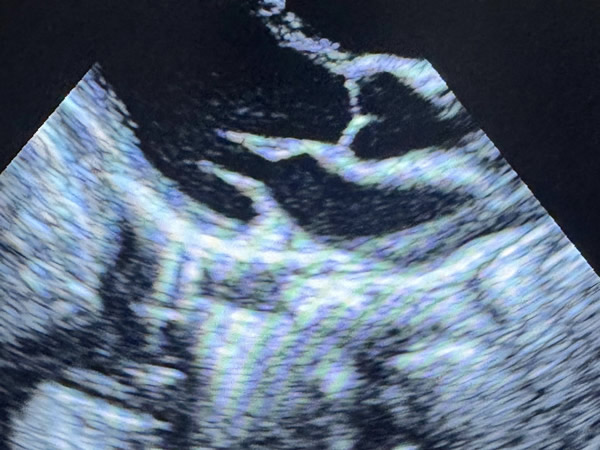

Válvula aórtica tetravalva en una paciente con comunicación inter auricular y ductus arterioso persistente